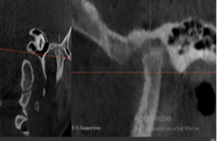

A través de los cortes tomográficos (Figura 3) se pudo observar que la rama mandibular derecha medía 43.85 mm y la izquierda 39.53 mm dando una diferencia de 4.34 mm lo que evidencia que la asimetría que presenta la paciente es a causa de la discrepancia de tamaño de las ramas mandibulares (A).

En el corte a nivel de la articulación temporomandibular izquierda se observó un aplanamiento del cóndilo con áreas de cambios osteoartríticos leves (B); en la articulación temporomandibular derecha el cóndilo se encuentra con una severa osteoartritis que muestra una imagen hipodensa a nivel condilar compatible con un quiste subcondral (C).

Diagnóstico de ATM: La paciente presenta una displasia discal sin reducción bilateral.